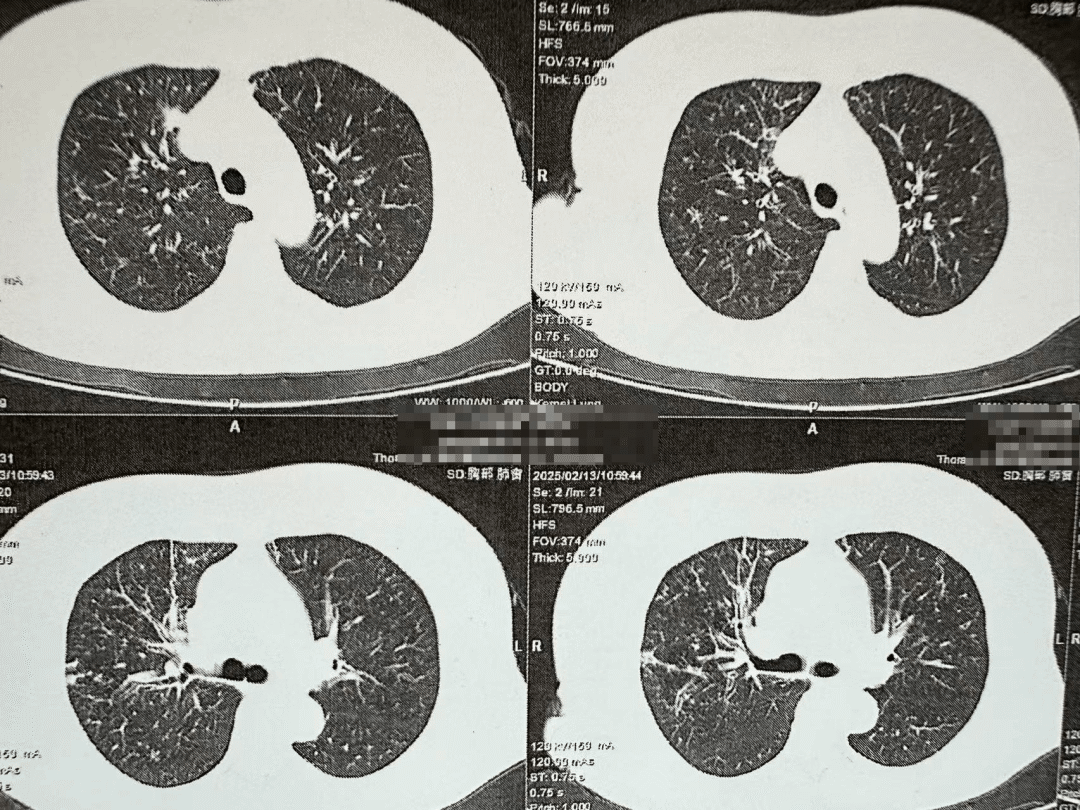

非HIV-PCP肺部影像

非HIV-PCP的早期癥狀與普通肺炎相似,但進展更快,48小時內(nèi)可能引發(fā)呼吸衰竭。有免疫缺陷病史(如腫瘤化療、器官移植、風濕免疫病長期用藥)等高危人群一旦出現(xiàn)持續(xù)發(fā)熱>1周,抗生素治療無效;干咳、進行性呼吸困難;血氧飽和度<93%等癥狀應立即到呼吸與危重癥醫(yī)學科就醫(yī),進行支氣管鏡肺泡灌洗檢查。